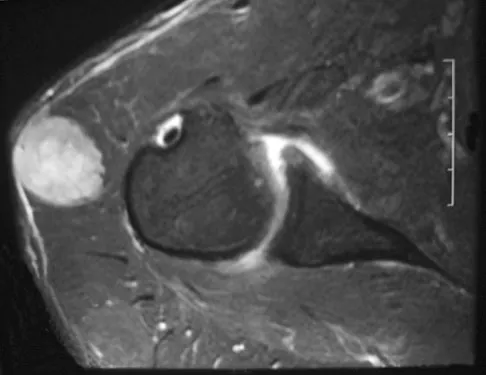

A 25-year-old man has had an insidious onset of left hip pain over the past 11 months. A radiograph, coronal MRI scan, and histopathologic specimens are seen in Figures 2a through 2d. What is the most likely diagnosis?

Explanation

Ewing's sarcoma is the second most common primary sarcoma of bone in children and young adults. It is a malignant round cell tumor with uncertain histogenesis. Sheets of uniform small round blue cells with a high nuclear-to-cytoplasm ratio and the absence of osteoid formation differentiate this histologic diagnosis from the other conditions. Immunohistochemical staining and molecular diagnostic studies are useful to verify the diagnosis.